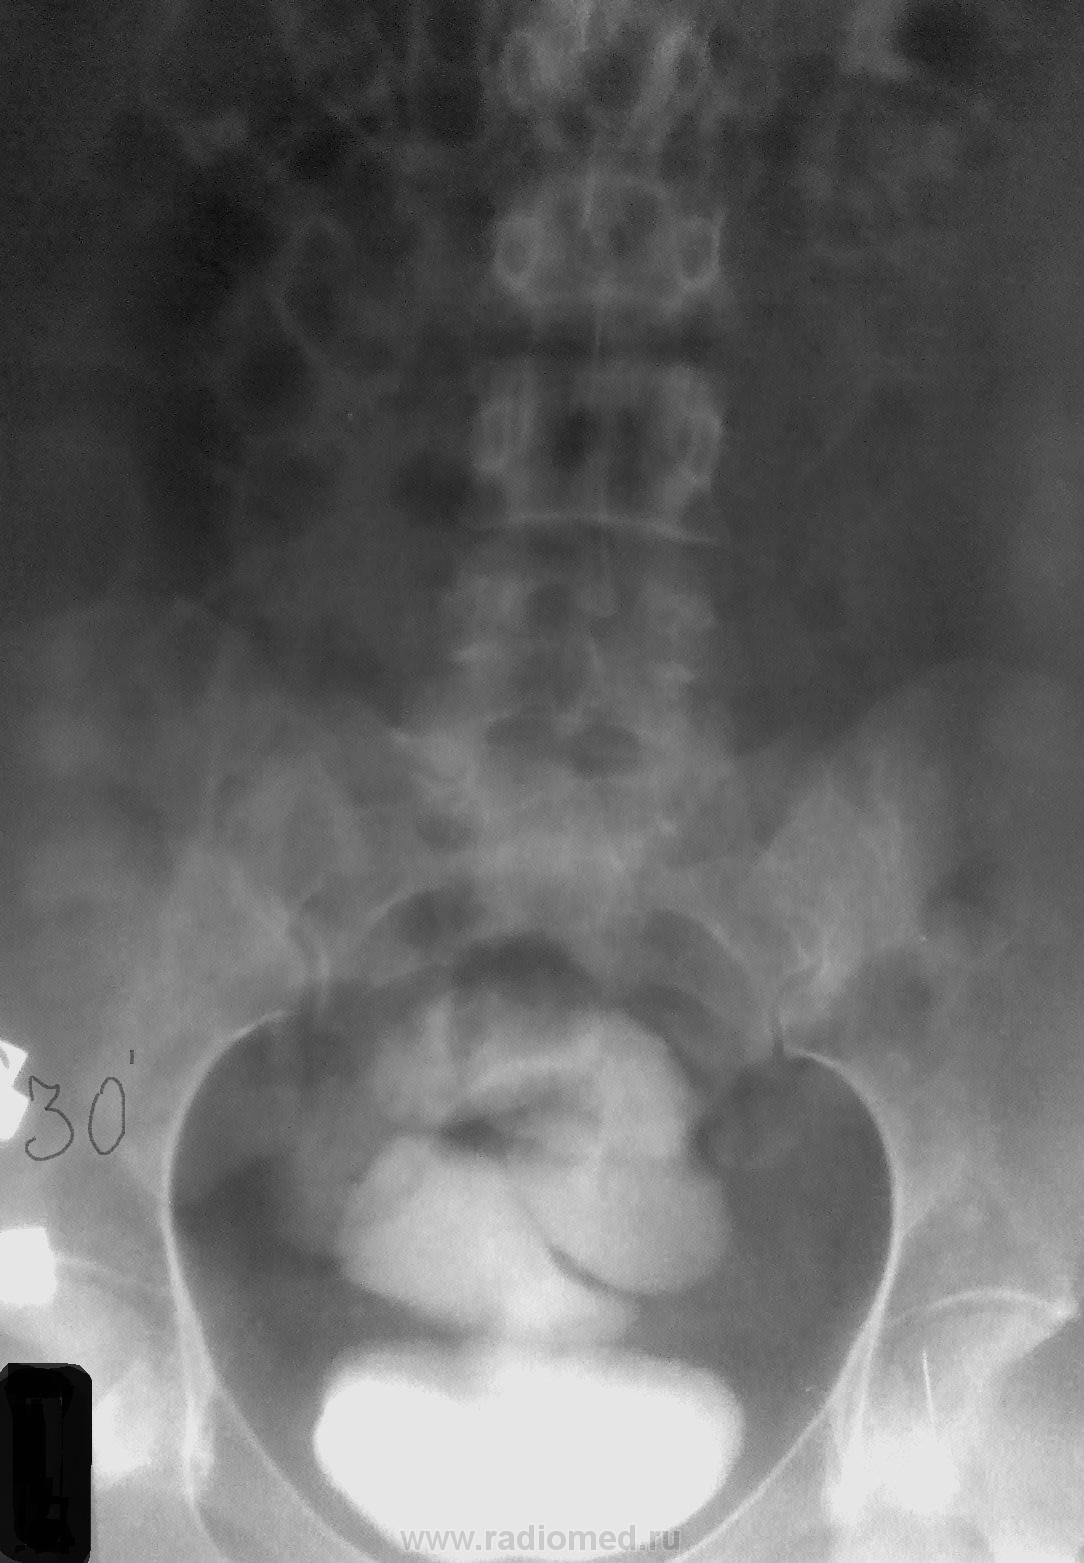

Но есть еще одна загадка....темы родственные, потом - в этой же ветке.

Вопрос - что бы это значило? Анамнеза не будет. С анамнезом тут и разгадывать нечего))))

Петрович тоже чешет репу: не видал такого. Похоже, как бы водорастворимый контраст в свободной брюшной полости, либо суспензия бария в ней.

Можно ещё предположить затёк контраста в забрюшинное пространство … свищ, полость в клетчатке.

Пока варианта два.

1. Рвзрыв мочевого пузыря.

2. Если травмы не было, то есть вопрос - это мужчина, или женщина?

1.Это женщина.

2. Да - это разрыв кишки.

3. Осталось указать причину....

А может кишка лопнула при ирригоскопии, произведённой уж очень агрессивно?surprise Я этого всегда страшно боялась, особенно у детей!crying

Мне нечего добавить....кроме того, что уже проведен ряд оперативных вмешательств...

В моей практике было нечто похожее...лет десять назад....женщине после ирригоскопии через час стало хуже...была прооперирована. Но там была опухоль на протяжении до 20,0 см с признаками распада...и эта микроперфорация была вполне обьяснима...просто она ускорила оперативное вмешательство. Но чтобы так - ...не видел и не слышал никогда до этого случая. По данным литературы - "возможна перфорация, как правило измененной толстой кишки...".